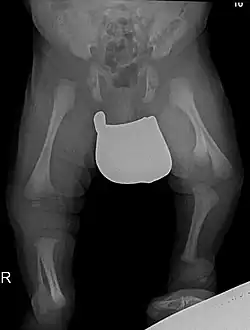

Das Gollop-Wolfgang-Syndrom ist eine sehr seltene Form einer Fehlbildung mit Spaltbildung in Hand oder Fuß (Ektrodaktylie) mit einseitiger Spalthand und einseitiger Gabelung des Oberschenkelknochens.[1]

Zusätzlich zur Hand-Ektrodyktylie und Femur-Bifurkation können Hypoplasie oder Aplasie der Tibia, Oligodaktylie oder Monodaktylie des Fußes vorliegen. Die Femurgabelung ist meistens einseitig.[1] Hinzu können Herzfehler, Gaumenspalte und Tracheo-ösophageale Fistel kommen.